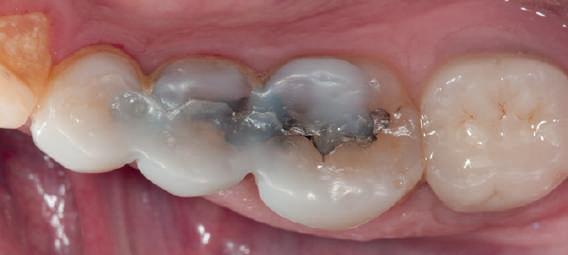

HYBRID COMBINATION RESTAURATIONS

Vonlay-uri: o alternativă conservatoare estetică la coroanele cu acoperire totală